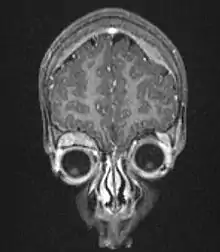

| Microscopic view of a typical neuroblastoma with rosette formation | |

On microscopy, the tumor cells are typically described as small, round and blue, and rosette patterns (Homer Wright pseudorosettes) may be seen. Homer Wright pseudorosettes are tumor cells around the neuropil, not to be confused with a true rosettes, which are tumor cells around an empty lumen.[26] They are also distinct from the pseudorosettes of an ependymoma which consist of tumor cells with glial fibrillary acidic protein (GFAP)–positive processes tapering off toward a blood vessel (thus a combination of the two).[27] A variety of immunohistochemical stains are used by pathologists to distinguish neuroblastomas from histological mimics, such as rhabdomyosarcoma, Ewing's sarcoma, lymphoma and Wilms' tumor.[28]